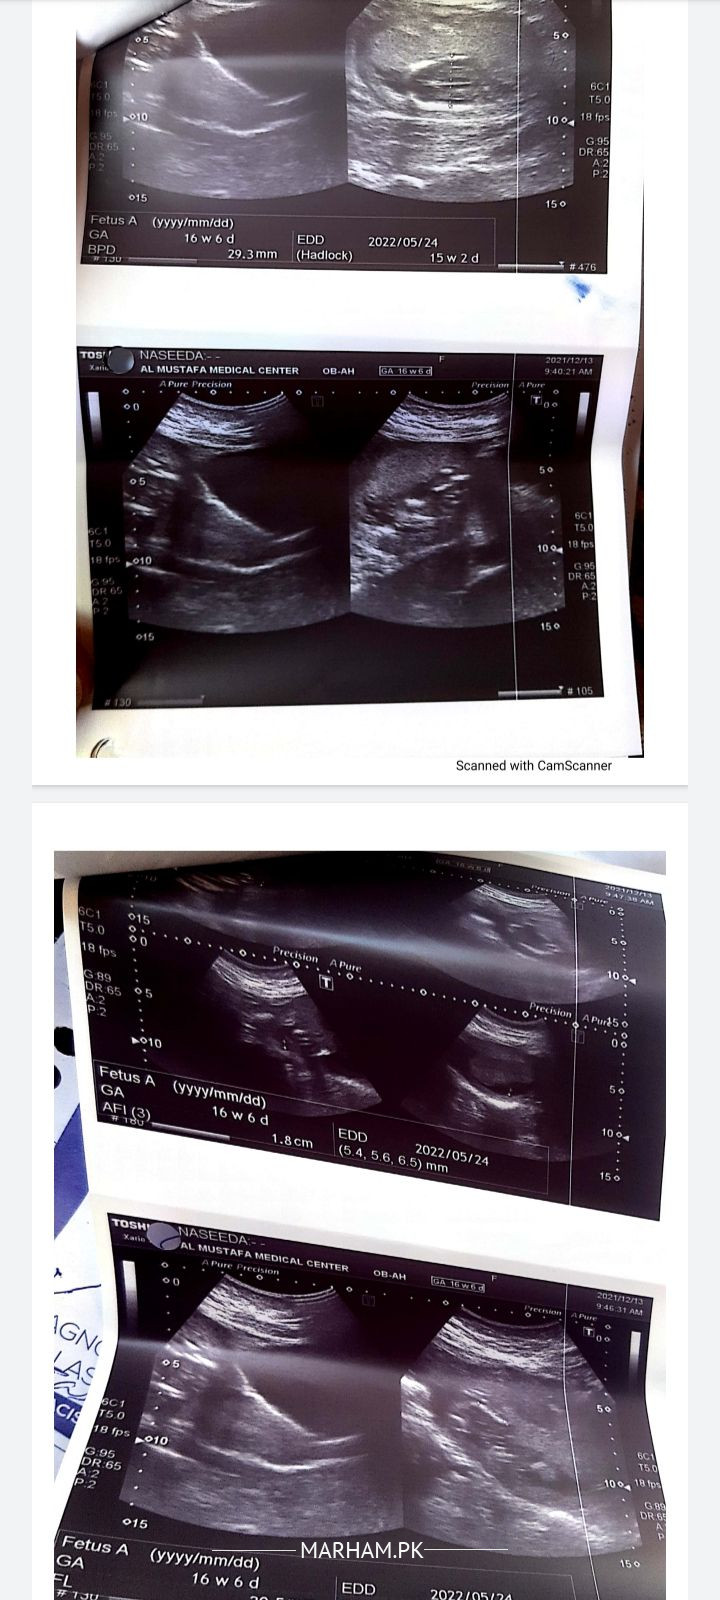

Asking For Self, Female 34, karachi

Assalamualaikum Dr reports are attached kia baby safe hai ya oprate krna hai please guide krdai

kindly come to clinic so that you can be assessed clinically.This report doesn't show any thing to operate because at this month you can't save the baby.why to go for surgery?

These reports are not by the qualified sonologist, have an U/S by some Prof of radiology, don't go for operation at this stage, show me at my clinic

Please don’t go for surgery at such early gestation. Visit any good gynaecologist for detailed proper evaluation

please get anomaly scan at 18 to 20 weeks by a radiologist. if the baby is alive u should wait and see. see gynaecologist to rule out leaking of baby waters.